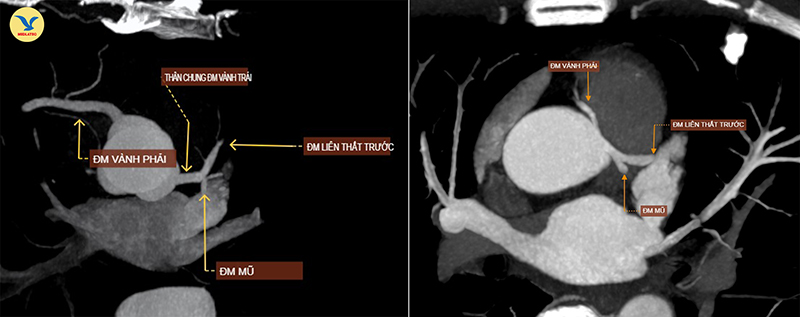

Hình ảnh chụp CTA. Ảnh trái: một người bình thường, hai nhánh động mạch vành xuất phát từ hai gốc riêng biệt. Ảnh phải: hai nhánh động mạch vành của bệnh nhân xuất phát chung một gốc

Với bất thường này, hai nhánh động mạch vành trái và động mạch vành phải của bệnh nhân xuất phát chung từ một gốc thay vì xuất phát ở hai vị trí riêng biệt, đồng thời bị kẹp giữa thân động mạch phổi và gốc động mạch chủ, khiến cho chúng bị hẹp bẩm sinh. Cụ thể ở ca bệnh này, nhánh động mạch vành phải bị hẹp khoảng 45% đường kính.